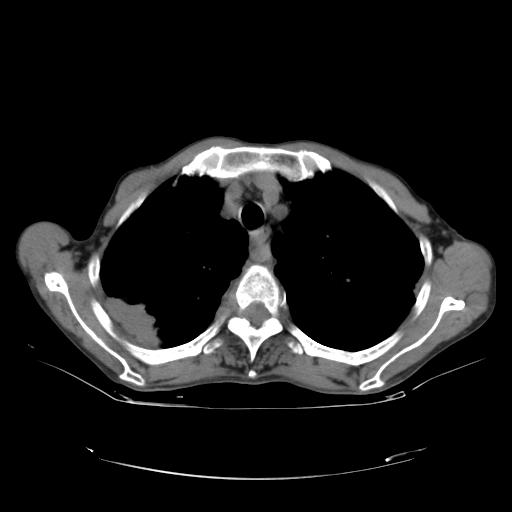

女,72岁,咳嗽一周余,突发右下肢无力二天。

pe:bp-140、80mmhg,精神可,伸舌居中,右上肢肌力正常,右下肢肌力0级,巴氏征+

来院做头颅+胸部ct平扫

胸部病变平扫35hu,增强强化至70hu

这个病人首先是胸部病变的定位到底是肺内还是肺外。仔细观察块影位于胸膜下,与胸膜间有透亮带,且近端血管未见明显推移而是引流样改变,形态分叶,说明这个病灶位于肺内胸膜下。很可能是腺癌,腺癌最易致颅内高密度转移灶。局部胸膜有侵犯。

本例颅内见多发大小不等高密度灶,有强化及水肿;另外,胸锁关节层面可能是第四胸椎及右侧肋骨起始部骨质欠连续,椎旁软组织肿胀,建议调骨窗观察。

诊断:右下肺癌伴颅内、胸椎、肋骨转移可能性最大。